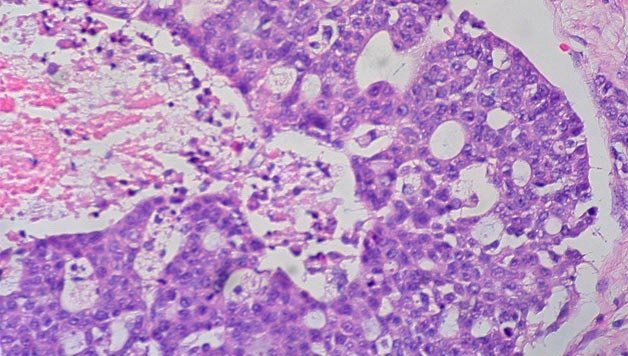

Minbizia gaixotasun hedatuenetariko bat da herrialde garatuetan. Denboraren poderioz, gure gorputzeko zelulak zahartuz joaten dira eta, halako batean, akatsen batengatik edo zahartu direlako, gaixotasunak ager daitezke. Beraz, minbizia, nolabait esan, norberaren zelulak gaiztotzea da. Gaurkoan Iker Badiola ikertzailearekin hitz egin nahi dugu, minbizia eta beronen metastasia zehazki zer diren adieraz […]